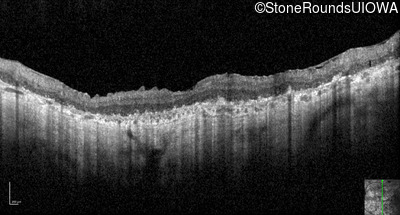

Optical Coherence Tomography - Right - Hand Motion 1' sc

Exemplar / OCT Stack